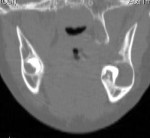

Cyst Associated with an Impacted Tooth in a Child

• Cysts either developmental or of unique dental tissue origin

• Tumors